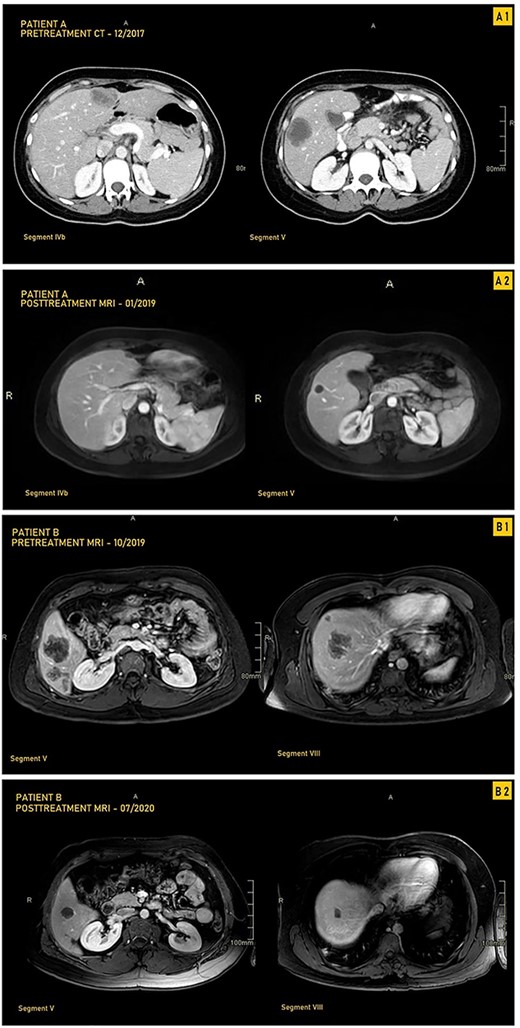

A 33-year-old female patient was diagnosed with a moderately differentiated invasive adenocarcinoma of the transverse colon with multiple bilobar liver lesions (Fig. 1A1 and Table 1). She underwent a laparoscopic subtotal colectomy, and the immunohistochemical analysis showed loss of MLH1 and PMS2 expression in tumor cells with retained MSH2 and MSH6, thus MMR-deficient (dMMR). She was started on FOLFOX (Oxaliplatin with 5-Fluorouracyl and Leucovorin) regimen with Avastin (Bevacizumab). Computed tomography (CT) scan was performed after her fourth cycle of chemotherapy and revealed an increase in size of the liver lesions (Table 1). She was started on pembrolizumab (19 cycles), and upon follow-up CT scans done every 3 months, there was a significant decrease in the size of the hepatic lesions (Fig. 1A2). She was reassessed and underwent liver resections of all her lesions. Final pathology was negative for residual carcinoma, with areas of necrosis and negative margins on surgical pathology.

CT and MRI images our two patients before and after treatment with pembrolizumab; (A1) Pretreatment MRI of our first patient in September 2017 showing most prominent lesions, located in Segments IVb and V, on axial enhanced CT after contrast administration; (A2) Posttreatment axial enhanced T1-weighted MRI of our first patient in January 2019 showing most prominent lesions located in Segments IVb and V; the lesion in Segment V is smaller, measuring 1.4 cm, and is completely necrotic; (B1) Pretreatment axial enhanced T1-weighted sequence MRI performed on 3Tesla field strength following gadolinium contrast administration in our first patient in October 2019 showing most prominent lesions, located in Segments V and VIII; the largest metastatic lesion is a 4.8-cm heterogeneously enhancing metastatic lesion in Segment VIII; (B2) Posttreatment axial enhanced T1-weighted sequence MRI performed on 3Tesla field strength following gadolinium contrast administration in the hepatobiliary phase in our second patient in July 2020, showing most prominent lesions located in Segments V and VIII; the largest lesion in Segment VIII decreases in size to 1.5 cm following treatment and is completely necrotic.